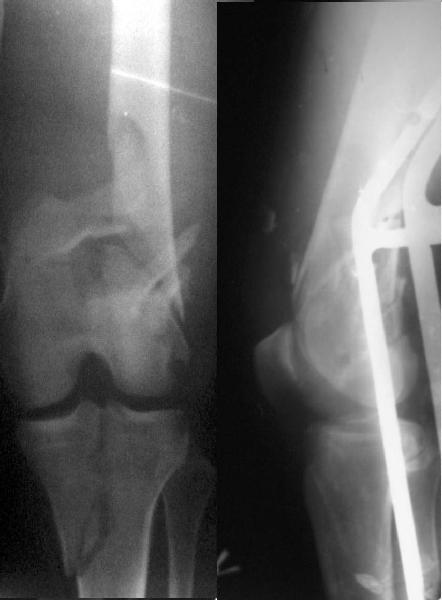

And why LISS is superior here than nail?

Look what we would have done.

I would not say that the LISS is superior to the nail. If I would, I had not post original mail. I wanted to generate discussion. Your option is a very viable one. I feel a little bit shaky the distal femur, but it is just gut feeling no science behind it. Any way nice fixation, congarts!

I presented the series at EuroTrauma in May. The "Distal Femur" section of the meeting was very interesting.